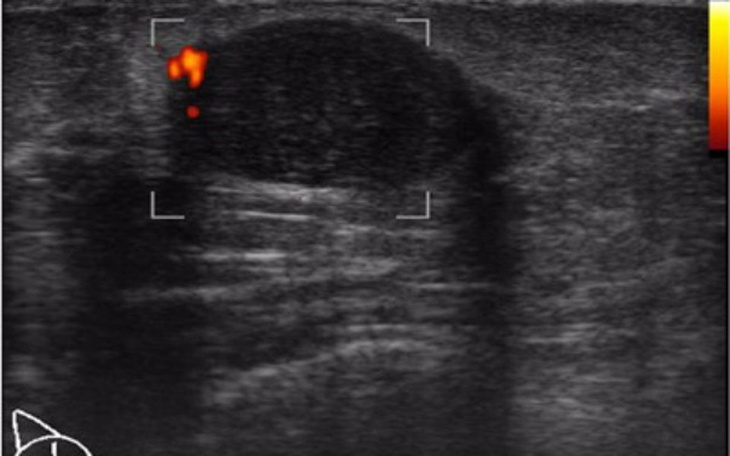

Witam mam 27 lat jestem po przejściach 7 lat temu straciłam rodziców mama zmarła na raka ojciec popełnił po 3 tygodniach od śmierci mamy samobójstwo ja opiekuje się bratem po ich śmierci. Nie mam ogrzewania ani ciepłej wody ubikacje też mam na dworze. Ale to nie jest najgorsze.... Okazało się że na piersi mam GUZA.... Który rośnie raka się dziedziczy szansa jest 50 na 50... Muszę mieć operacje usunięcia guza ale operacje na kasę chorych mam na marca ponieważ nie ma prędzej miejsca... Potrzebuję zebrać pieniądze na operację która kosztuje 9 tys muszę to zrobić jak najszybciej bardzo się boję o swoje życie i o to że moge nie doczekać operacji refundowanej ... A także ze zostawię brata samego... Bardzo proszę ludzi dobrej woli i osoby które wiedzą co przeżywałam o POMOC :(